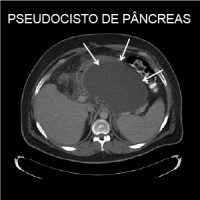

Pseudocisto de pâncreas

A formação de um cisto (líquido no interior), podendo ser únicos ou múltiplos, e de tamanho variado, podendo se formar dentro e fora do pâncreas. A parede do pseudocisto é formada pelas estruturas adjacentes, como o estômago, pâncreas e o intestino grosso, não sendo assim uma verdadeira parede.

Pode ser causado após um episódio de pancreatite aguda (ingesta de bebida alcoólica e pedra na vesícula), devido ao acúmulo de liquido ao redor do pâncreas após a inflamação, ou devido à ruptura de um ducto pancreático, seja por um trauma ou por pancreatite aguda ou crônica. Possui concentração elevada de enzimas pancreáticas em seu interior. Geralmente se forma dentro de um prazo de quatro semanas do episódio de pancreatite aguda.

Aproximadamente 10% dos pacientes com pancreatite podem apresentar pseudocistos.

A ecografia pode demonstrar a presença do pseudocisto, assim como sinais de pancreatite crônica (calcificações e atrofia do pâncreas) ou aguda, dilatação do ducto pancreático, e aumento do tamanho do pâncreas.

A Tomografia e/ou Ressonância determinam se há pseudocisto do pâncreas, sua localização, assim como a presença de sinais de pancreatite aguda e crônica. Podem ajudar, juntamente com a história do paciente, a diferenciar o pseudocisto de tumores císticos do pâncreas.